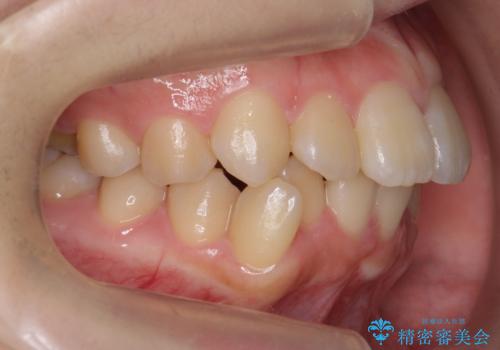

奥歯のかみ合わせも妥協しない インビザライン治療

インビザライン治療は主に奥歯のかみ合わせが大きな問題がない場合は特に問題なく終了しますが、今回のケースのように奥歯のかみ合わせが悪い場合、しっかり治らないことがあります。

患者様が気づかない範囲で妥協して終わるということをせず、しっかり奥歯に部分矯正を用いて大きな問題を解決してからインビザライン治療に入りました。

奥歯までしっかり咬ませたい場合、矯正医を選ぶ場合は注意が必要です。

妥協したゴールのみを目指すドクターではなく、時にはワイヤー部分矯正を使用してこだわりをもって治すドクターを選ぶとしっかり治るかもしれません。